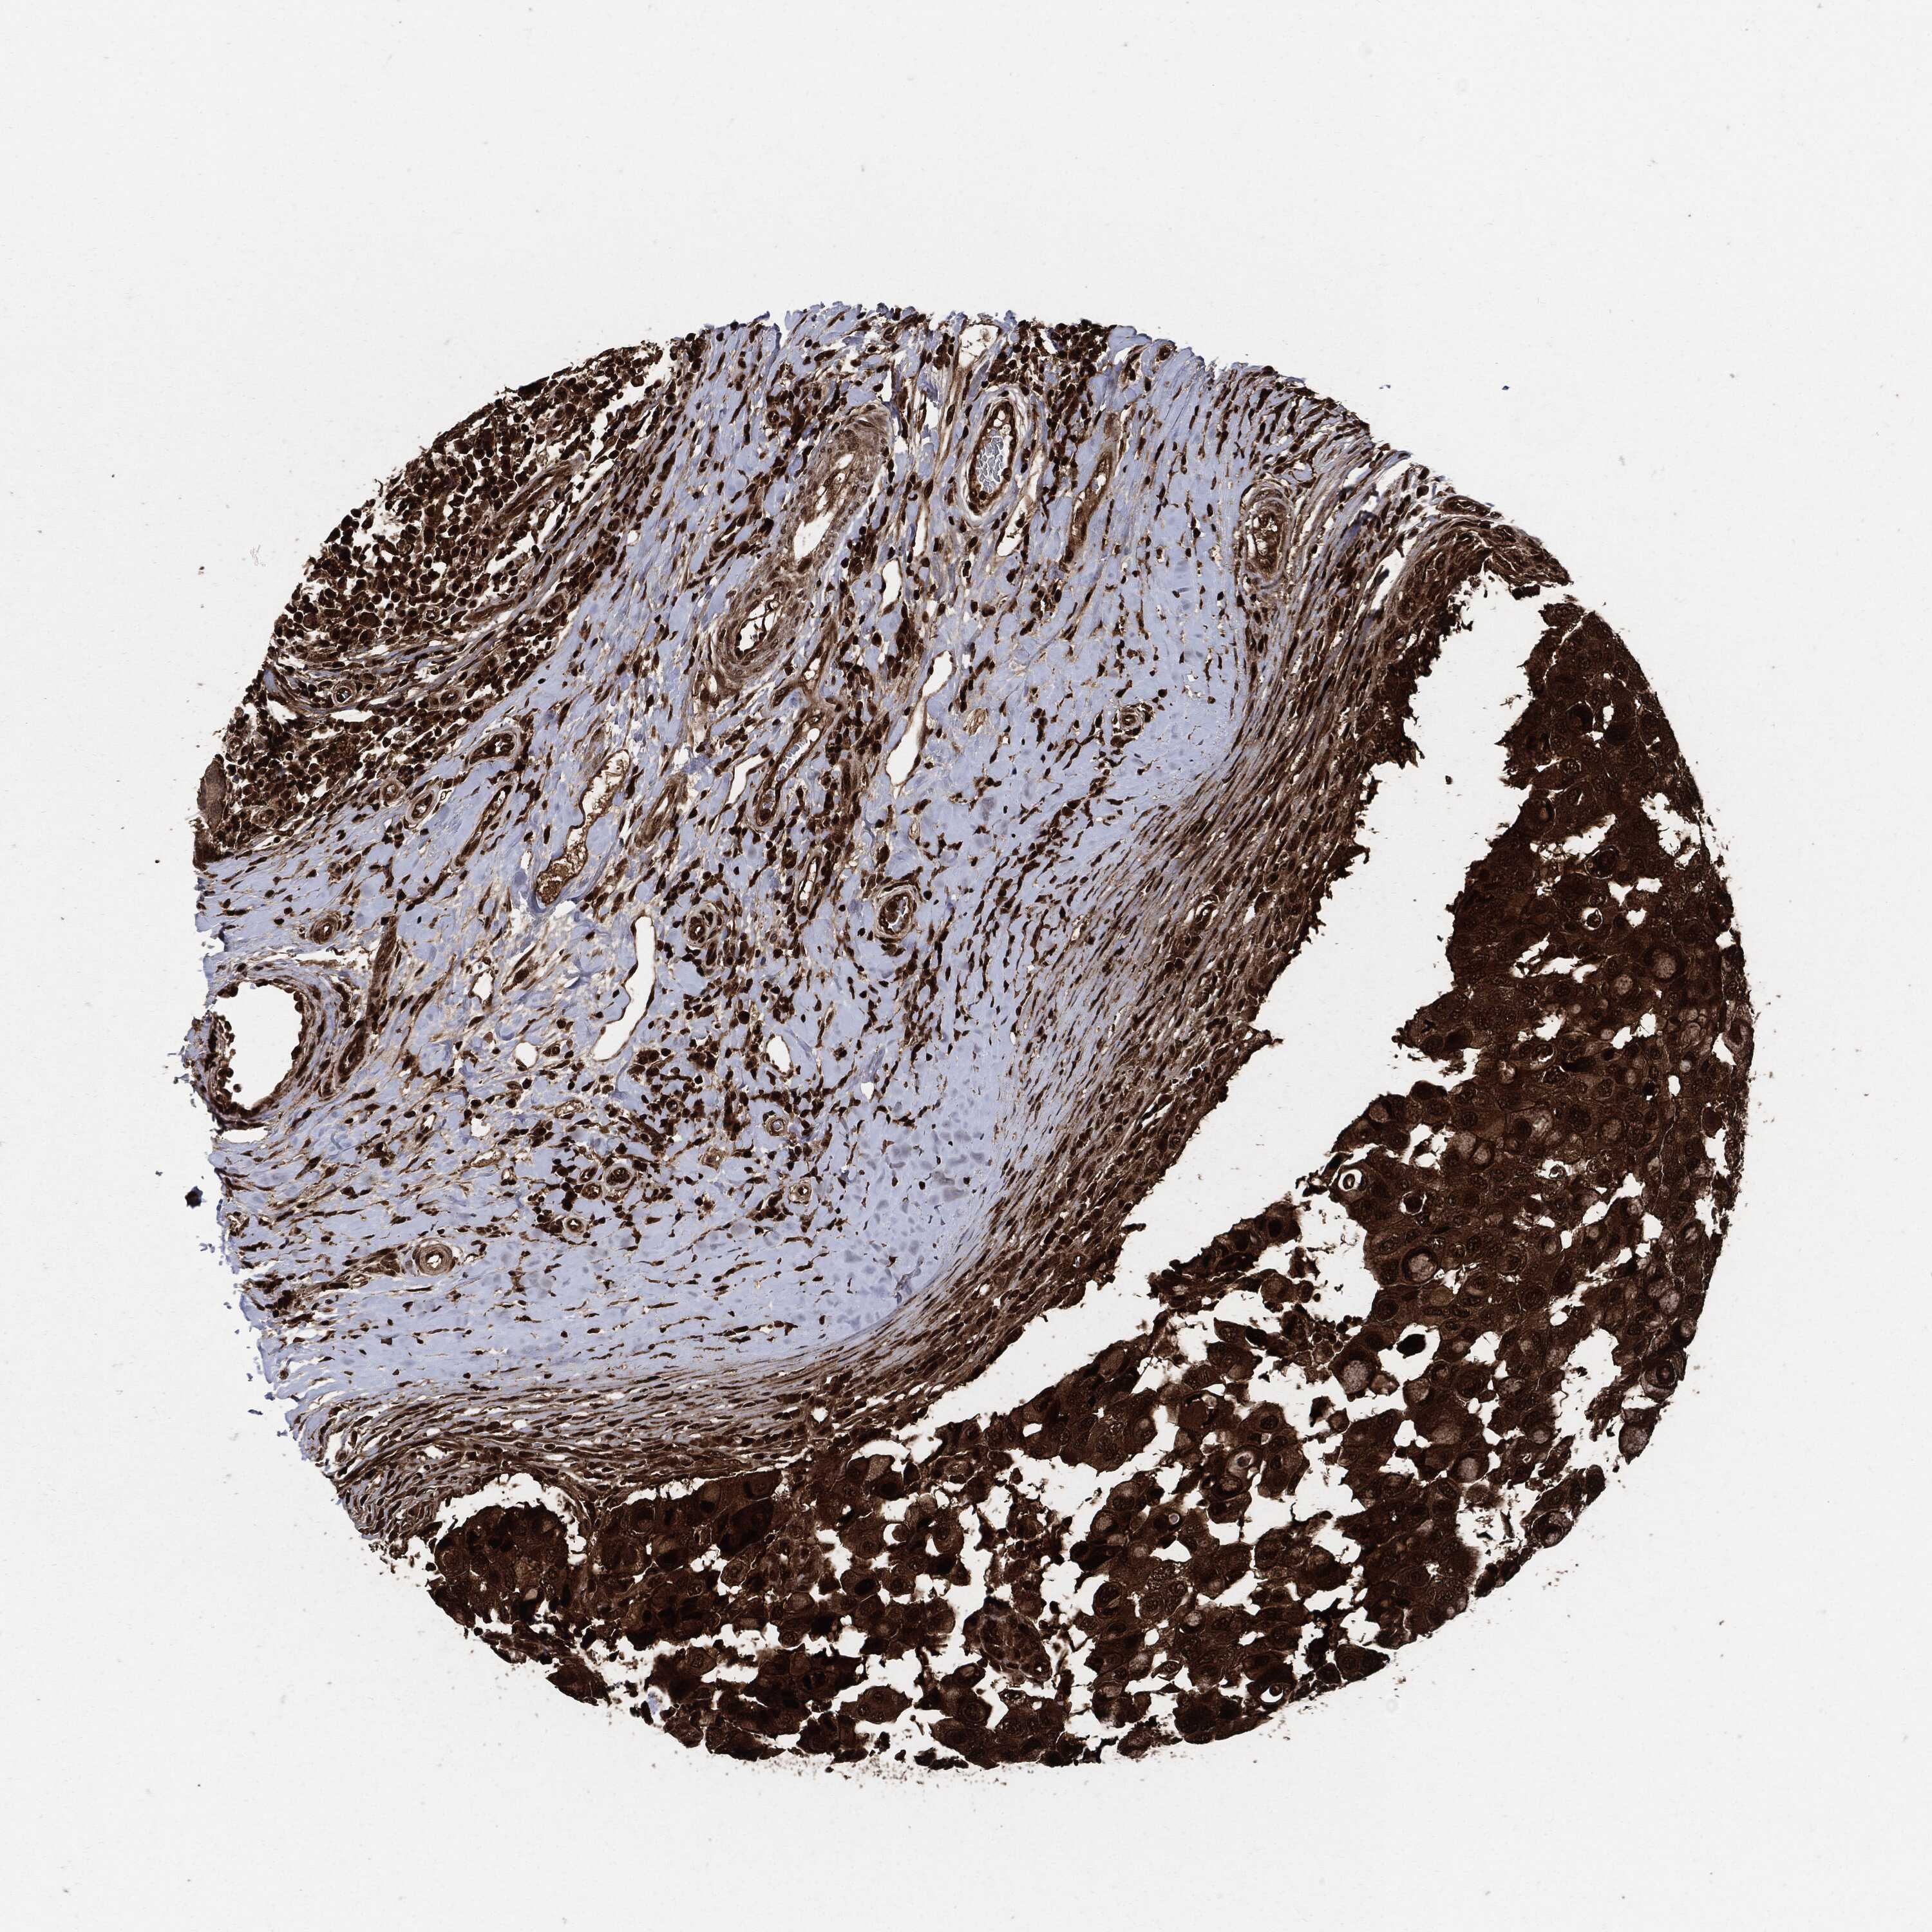

BRCA TCGA BRCA VALIDATION PROTEIN EXPRESSION

ANTIBODIES

AND

VALIDATION